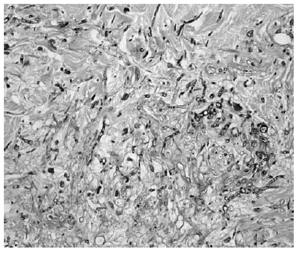

La biopsia de piel mostró discreta espongiosis y exocitosis linfocitaria en la epidermis, observándose en dermis papilar y reticular una intensa infiltración por elementos fúngicos en forma de hifas tabicadas y no tabicadas, en ocasiones bifurcadas, y por estructuras de tipo levaduriforme (fig. 2). Estas hifas tenían afinidad por las paredes vasculares a las que invadían (fig. 3). La respuesta inflamatoria acompañante es prácticamente nula. En el cultivo de la biopsia cutánea se identificó un hongo del género Fusarium, siendo los hemocultivos, cultivos del catéter y de esputo negativos.

Fig. 3.--Detalle de los hongos invadiendo la pared un vaso (PAS)